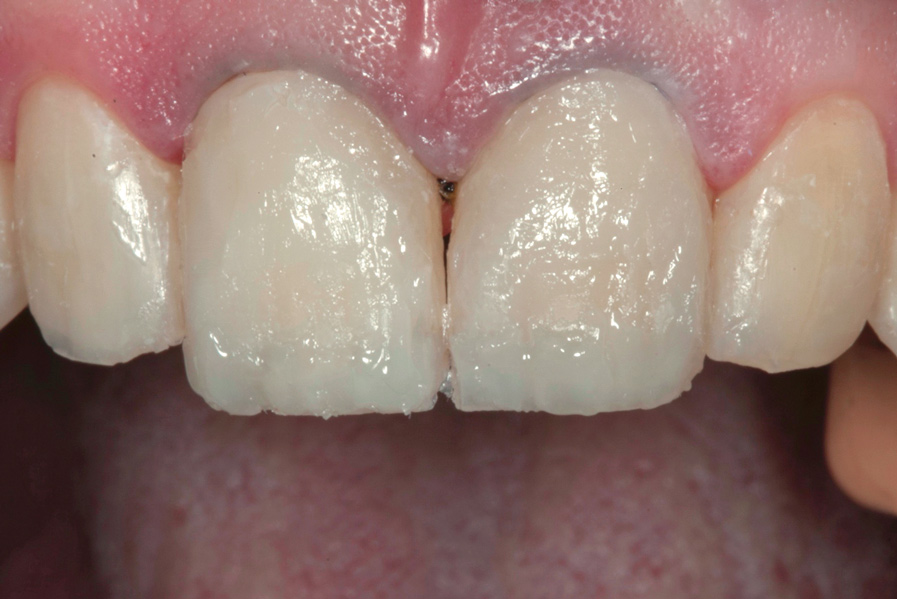

(11.) Postoperative retracted view.

Figure 11

After the composite veneers were finalized, impressions were taken for a monolithic lithium disilicate crown on tooth No. 12. This was placed during a subsequent appointment, and occlusal equilibration was carried out. The patient returned for final photographs a couple of weeks later (Figure 10 through Figure 14).